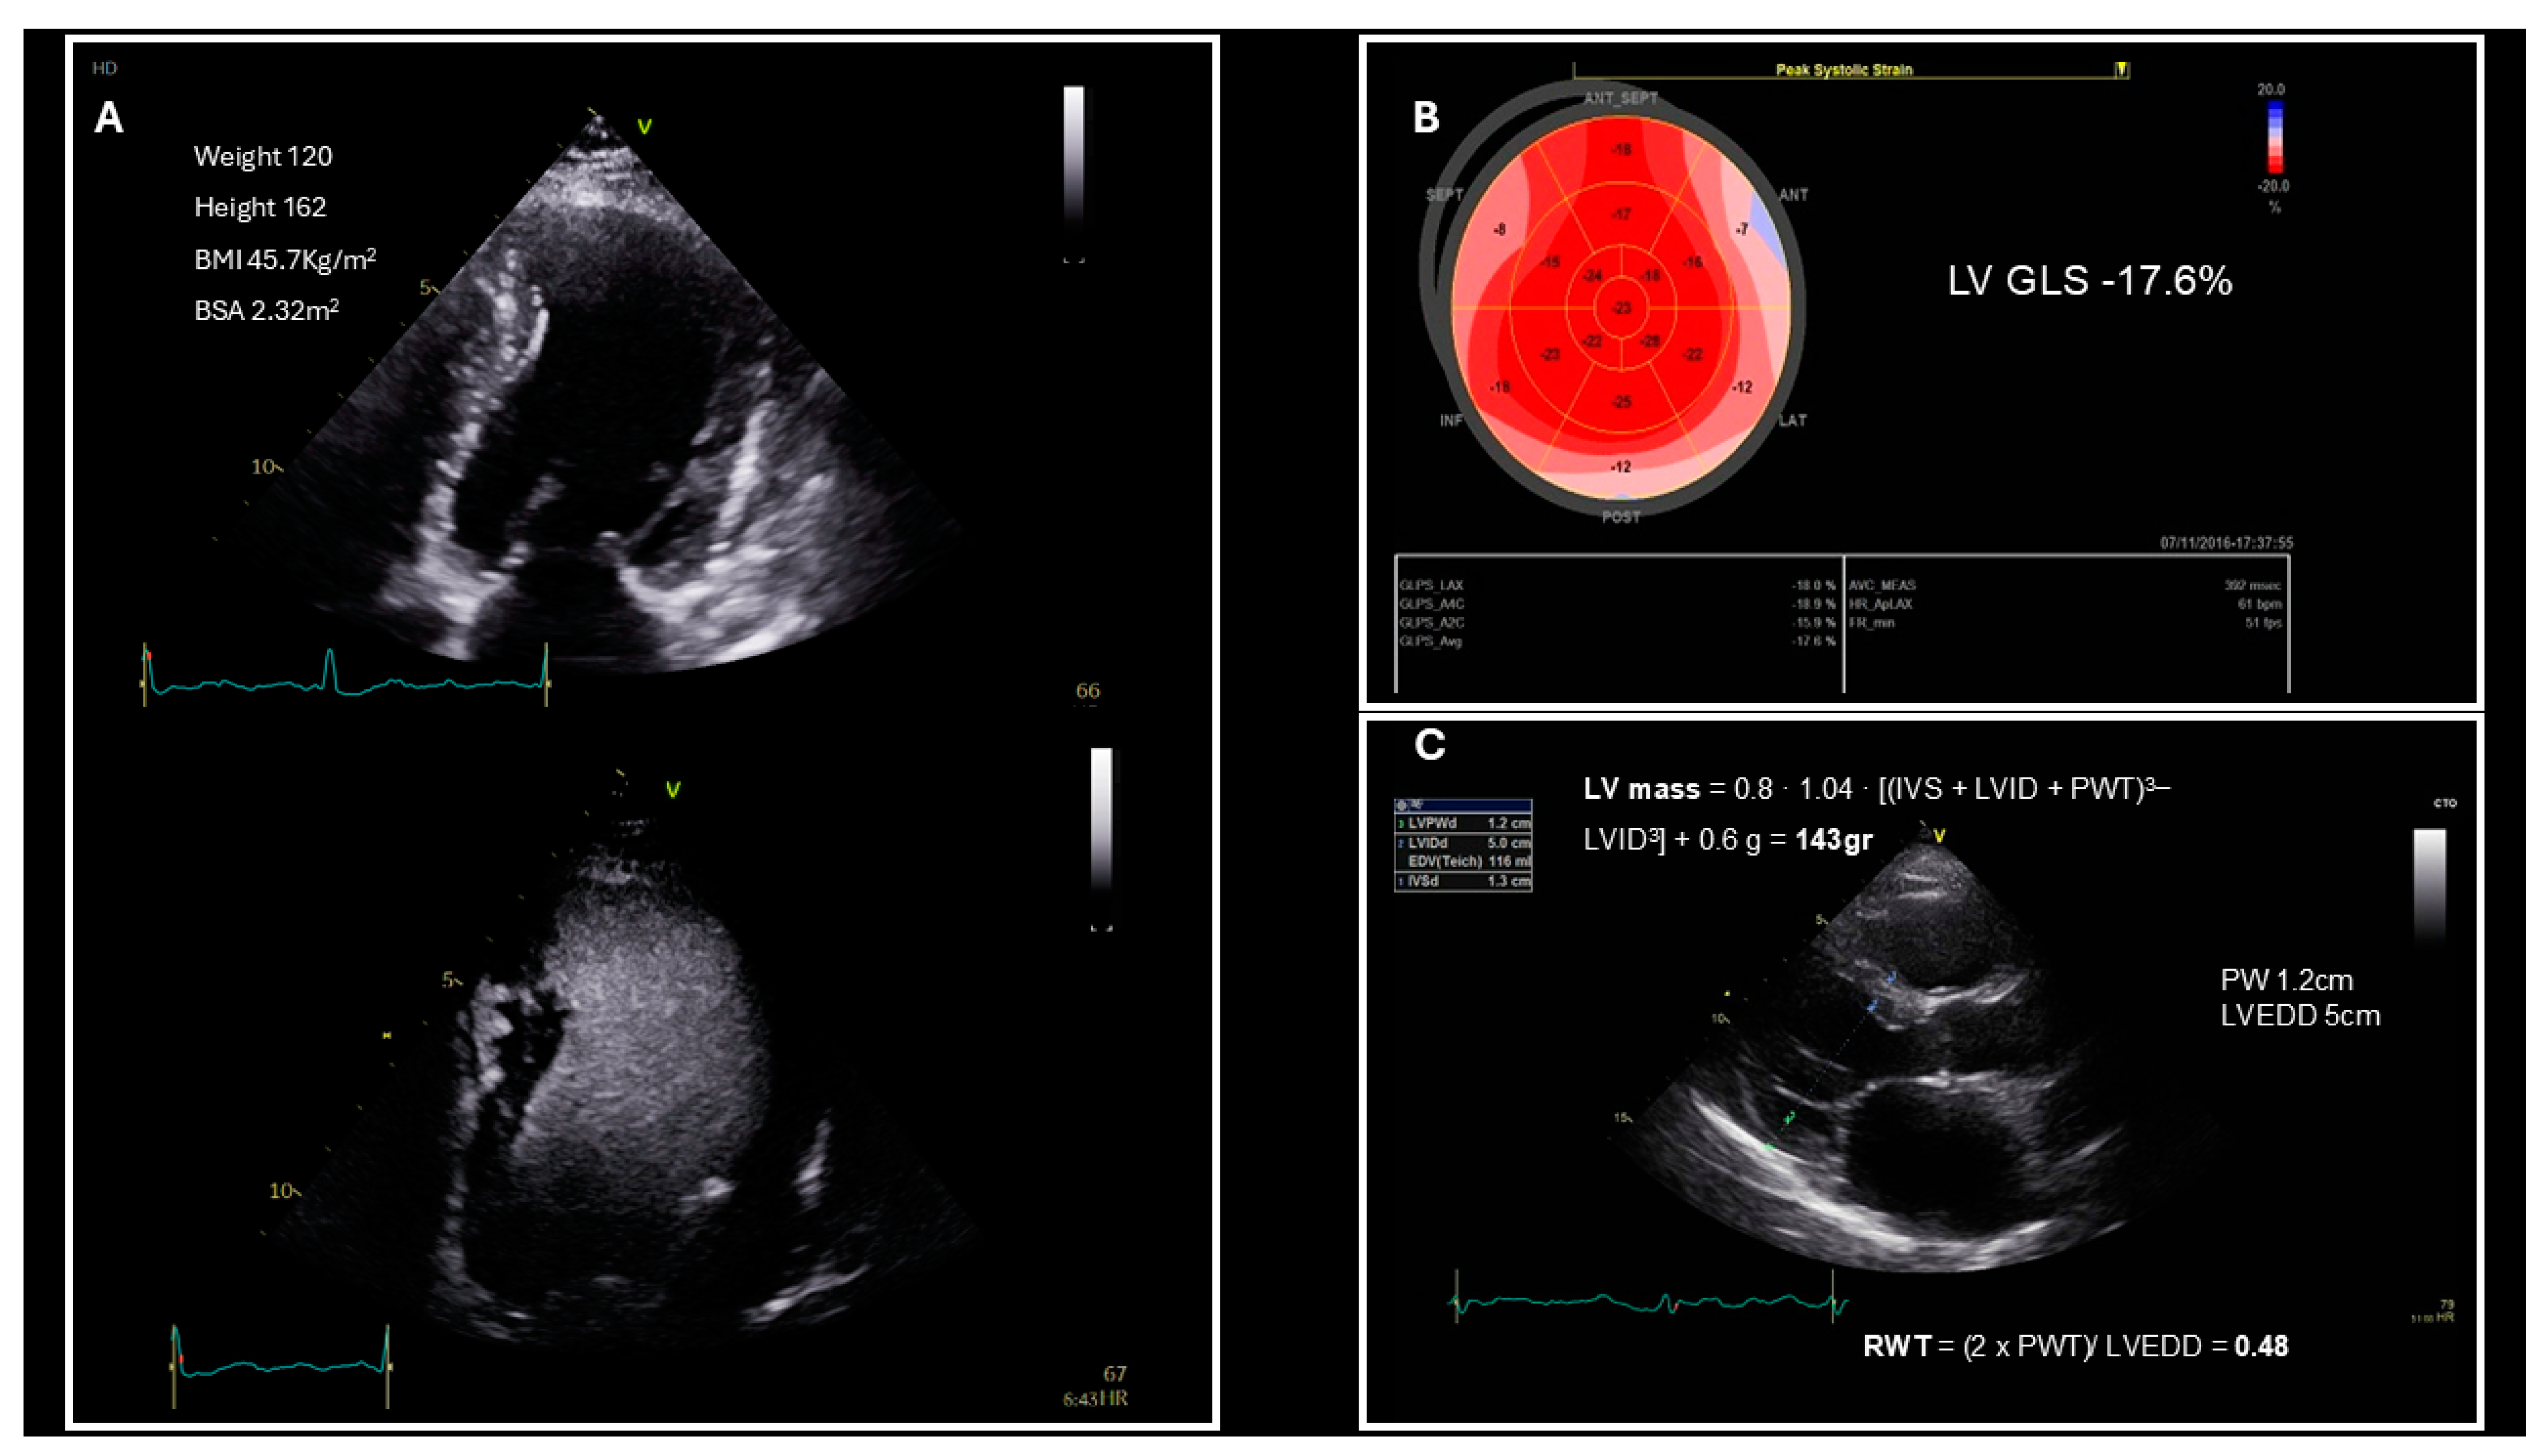

2. HFpEF Diagnosis Based on Guidelines

3. Left Ventricular Structure and Systolic Function Evaluation in Patients Who Are Obese